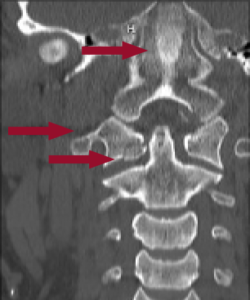

Figure 1: CT showing a C1 fracture with evidence of retroclival hemorrhage extending through foramen magnum. Facets at C1–C2 are no longer aligned.